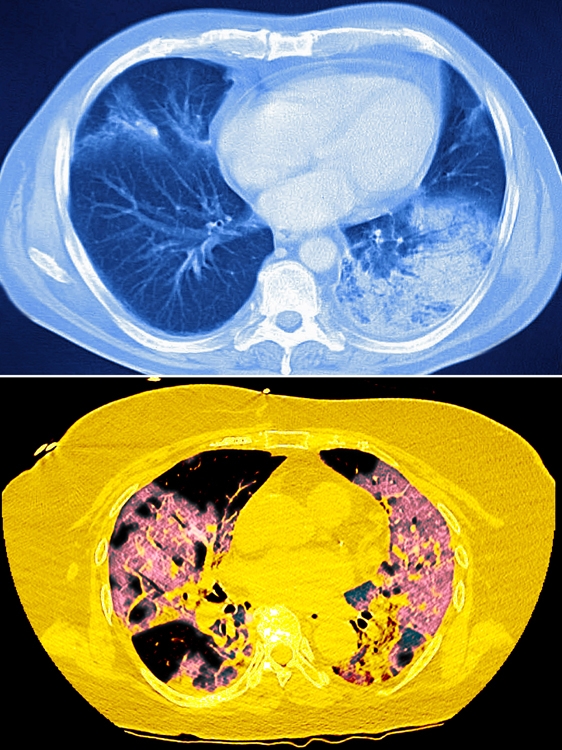

コロナによる間質性肺炎(下)では両方の肺全体に白い影が広がる(写真/GettyImages、時事通信フォト)

まず肺とは、気管から気管支へとつながった末端にある臓器で、3億個ほどある風船状の「肺胞」で成り立っている。肺胞の隙間には血管やリンパ管があり、それらを支える組織を「間質」という。